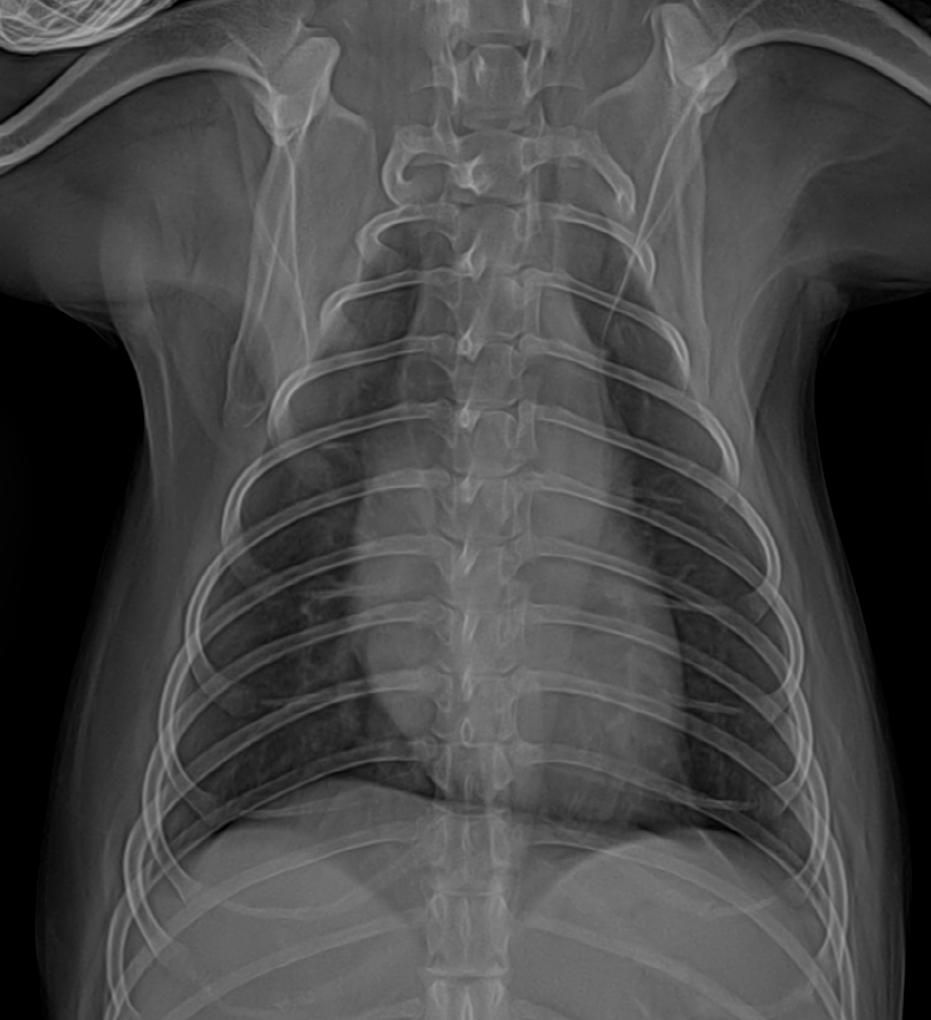

강아지 엑스레이 확인부탁드려요ㅠㅠ

안녕하세요 14살 강아지 투시촬영 엑스레이 사진인데요 분홍색 으로 체크한 동그랗게 있는게 무엇인가요? 종양인가요? ㅠㅠ뭔가요

위에 있는 물이 옆으로 눕힐때 유문부에 쌓인상태로 찍혀서 둥글게 보이는 대표적인 허상입니다.

정상입니다.